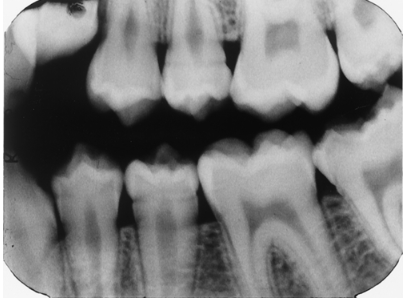

Note the occlusal anatomy of the occlusal surface of the mandibular 2nd molar that has just erupted. Now look at the maxillary 2nd premolar and lower premolars. What is your assessment of these teeth?

enamel hypoplasia

rampant caries

dentin dysplasia

Don't look at me, I don't diagnose.